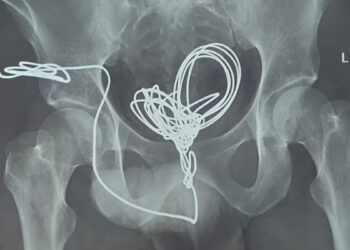

വെറും 26 വയസ് മാത്രം പ്രായം, ഒരു നിമിഷത്തെ ഡോക്ടറുടെ അശ്രദ്ധയിൽ സുമയ്യയുടെ ശിഷ്‌ടകാലം നെഞ്ചിനുള്ളിൽ കുടുങ്ങിയ ഗൈഡ് വയറുമായി!! വയർ പുറത്തെടുക്കുന്നത് ‘റിസ്ക്’, ശസ്ത്രക്രിയയ്ക്കിടെ രക്തക്കുഴലുകൾ പൊട്ടാൻ സാധ്യത- മെഡിക്കൽ ബോർഡ്

തിരുവനന്തപുരം: ശസ്ത്രക്രിയ നടത്തിയ ഡോക്ടറുടെ അനാസ്ഥമൂലം സുമയ്യയ്ക്ക് നെഞ്ചിനുള്ളിൽ കുടുങ്ങിയ ഗൈഡ് വയറുമായി കാലം നീക്കേണ്ടി വരുമെന്ന് മെഡിക്കൽ ബോർഡ്. ജനറൽ ആശുപത്രിയിൽ തൈറോയ്ഡ് ഗ്രന്ഥി നീക്കം...